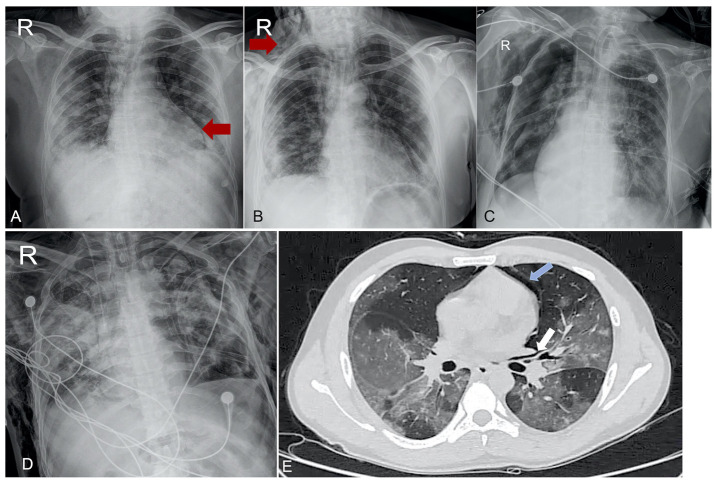

Results: Of 825 patients admitted to COVID ICU, 40 developed pulmonary barotrauma, with a mortality rate of 85%. The mean ± SD PaO2/FiO2 was 96.76 ± 27.78 mmHg. Thirty-nine patients received steroids, 37 developed secondary bacterial infection of the lower respiratory tract with one or more organisms. Acinetobacter baumannii (n = 15), Klebsiella pneumoniae (n = 10), and Pseudomonas aeruginosa (n = 8) were the commonest isolates. Ten patients developed pneumomediastinum, of which 6 patients had subcutaneous emphysema along with pneumomediastinum, and 2 patients developed isolated subcutaneous emphysema. The remaining 28 patients developed pneumothorax.The mean (±SD) for static respiratory system compliance (Crs) for patients on mechanical ventilation on the day of barotrauma was 19.3 (±10.5) mL/cmH2O.

Abstract Image